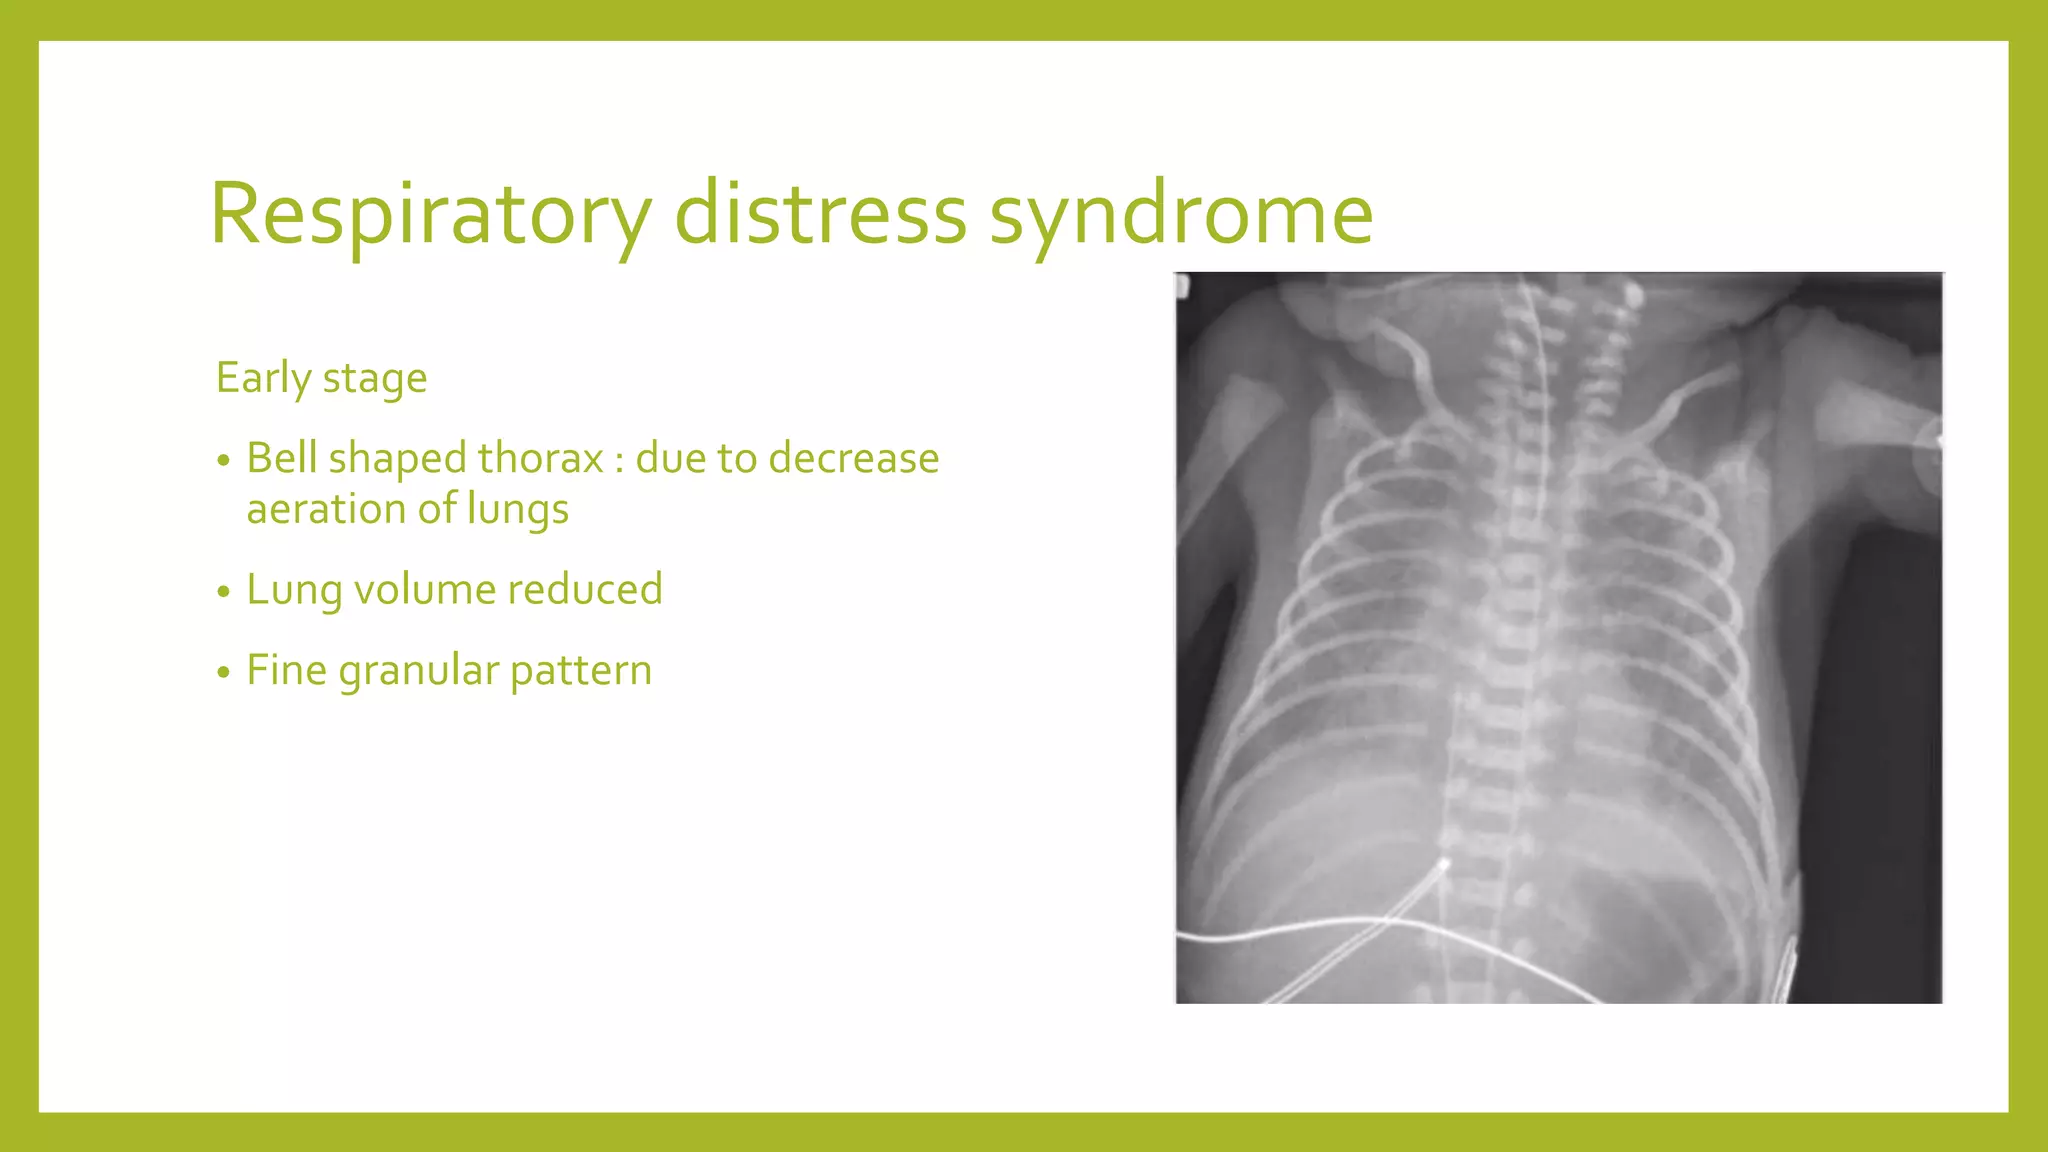

The document provides guidance on approaching and interpreting chest x-rays (CXR). It outlines steps to check the name, date and quality of the film, systematically scan the CXR looking for abnormalities, and determine if the lungs appear too white or black. Specific signs are described to help localize abnormalities, including the cardiac silhouette sign and pleural effusion signs. Examples are given of respiratory distress syndrome, tetralogy of fallot, transposition of great arteries, and total anomalous pulmonary venous return. The take home message is to summarize positive findings, compare to prior CXRs if available, and confirm findings with a radiologist.